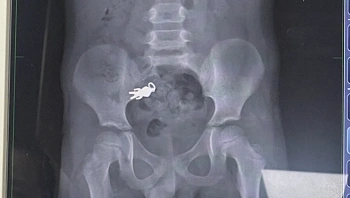

חדשני: רופאים השתמשו בקונדום כדי לרפא אדם שבלע מצית